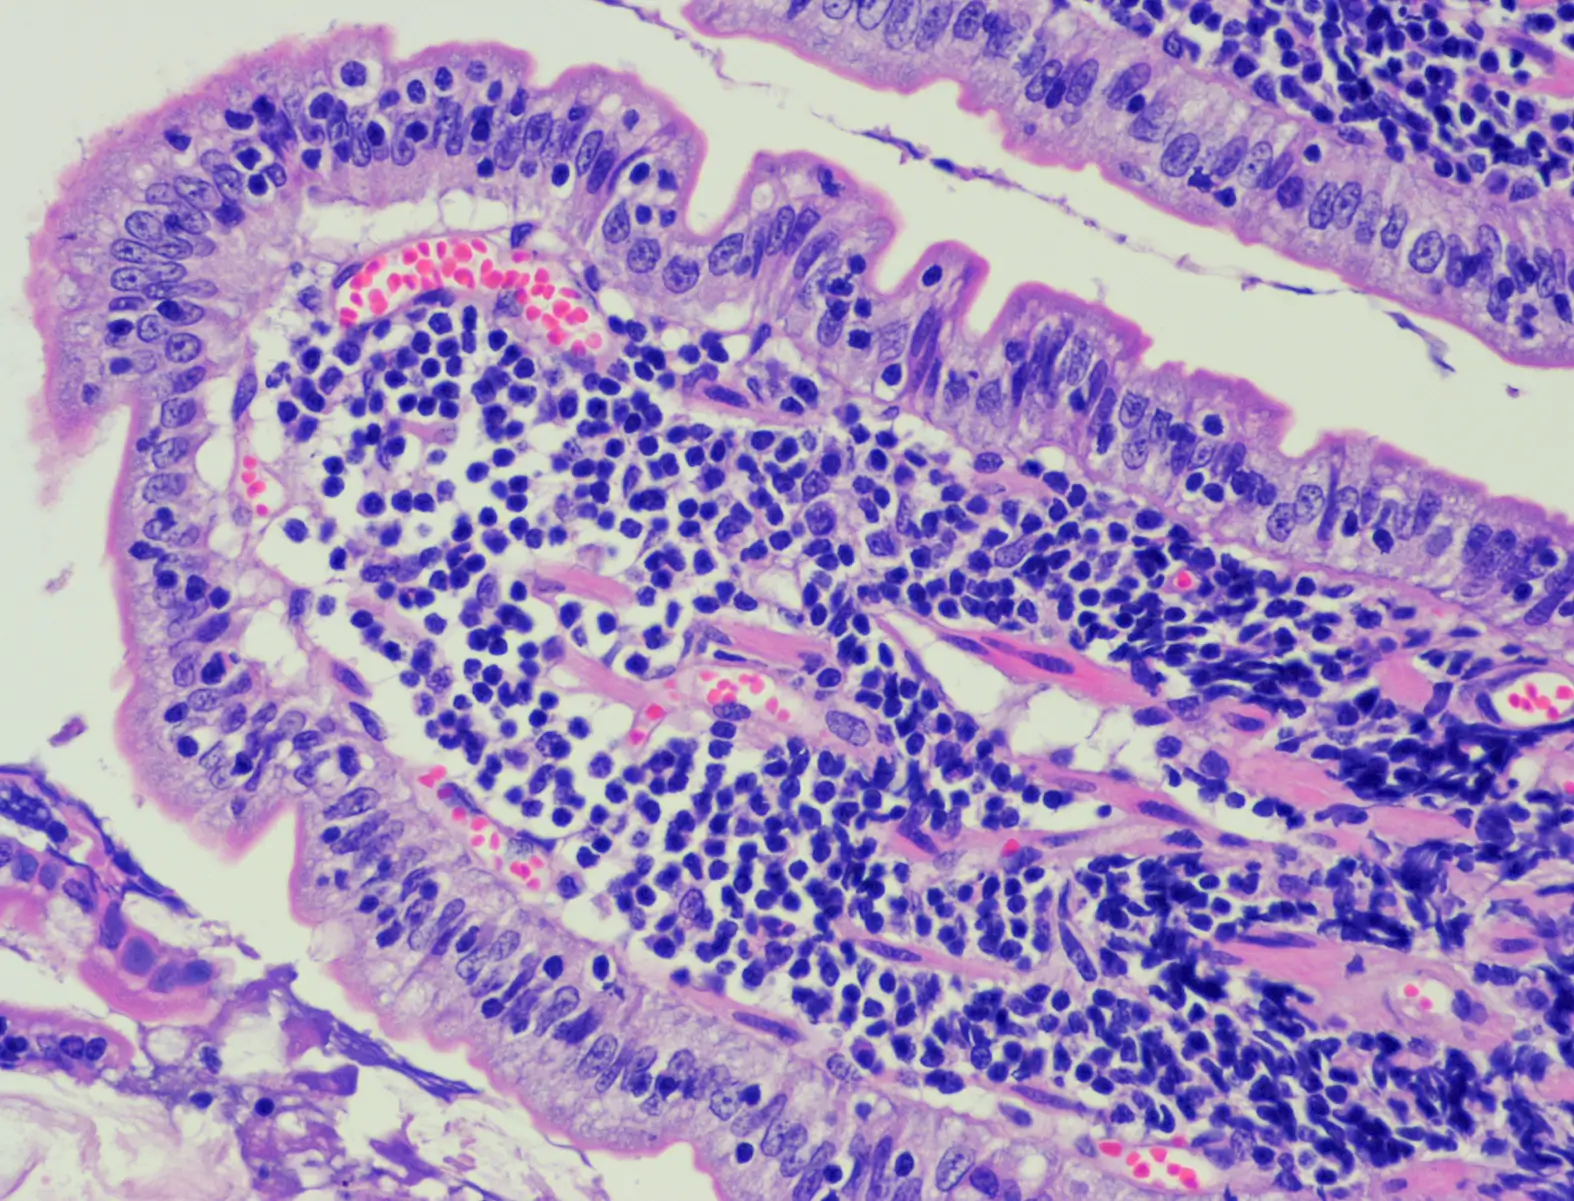

病理検査

超音波検査下で採取した細胞や内視鏡検査や開腹手術で採取した組織から確定診断を行います。